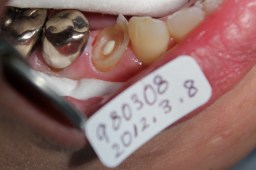

2008年08月18日:初診 44番の隣接面カリエス 主訴:歯がしみる。 下記:同部の拡大 |

虫歯(軟化象牙質)が大きく深いので むし歯をすべて除去すると、神経(露髄)する 可能性が大きい。 神経を取らないでいいようにフッ素洗口(NaF) を指示。 目的 第二象牙質の促進と虫歯の回復。 |